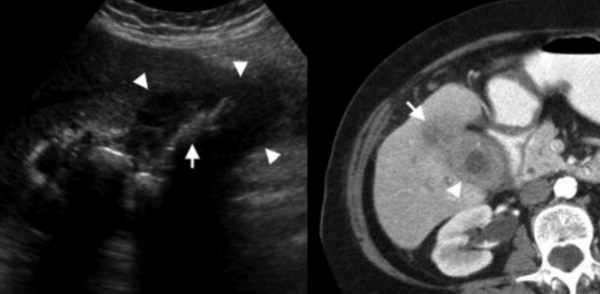

Ксантогранулематозный холецистит — это воспалительное заболевание, характеризующаяся тем, что в стенке желчного пузыря образуются ксантомы и гранулемы. При исследовании выявляют утолщение стенки желчного пузыря, уменьшение органа в размере, а также интрамуральные узелки, которые визуализируются, как гипоэхогенные включения на УЗИ и гиподенсные на компьютерной томограмме. Данные включения схожи с включениями при карциноме желчного пузыря.

УЗИ и КТ желчного пузыря. Ксантогранулематозный холецистит. Слева на УЗИ визуализируется (помечено стрелками) утолщение стенки желчного пузыря с интрамуральным включением и с камнем в просвете органа. Справа на КТ выявляется утолщение стенки с гиподенсными включениями.

Выше представлено КТ пациента 71 года с ксантогранулематозным холециститом. Постконтрастное КТ. Визуализируется утолщение стенки желчного пузыря с включениями, которые соответствуют абсцессу или фокусам воспаления.